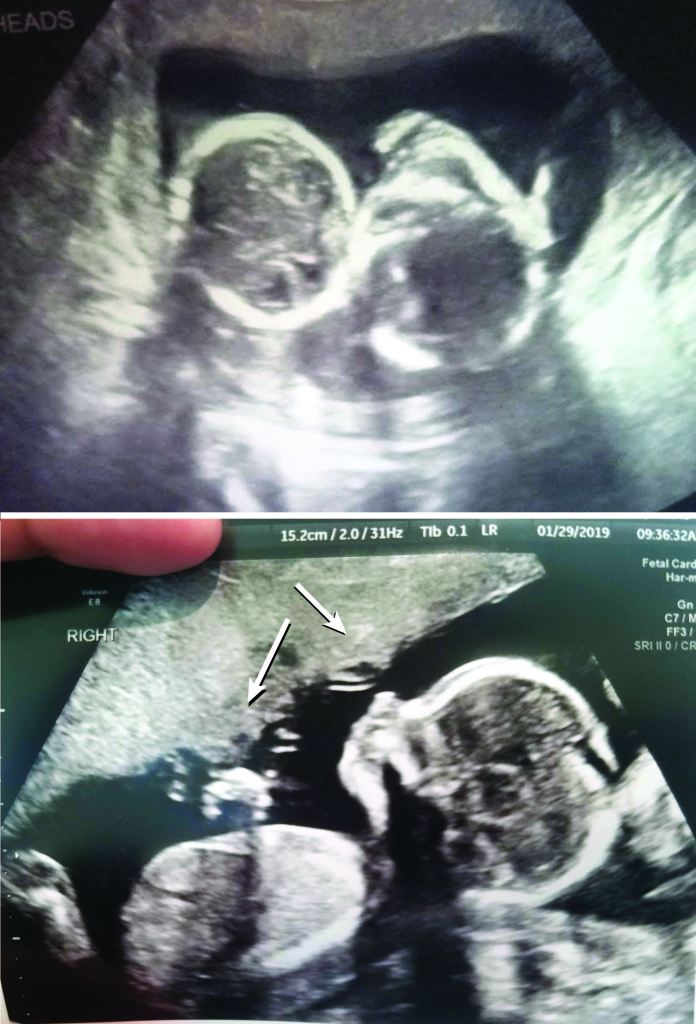

He scrutinized the ultrasound. The twins were clearly monochorionic; he was looking for the intervening membrane to confirm they were diamniotic.

“I’m not seeing an intervening membrane,” he told the tech. The mood in the room suddenly changed. The smile on my face flipped a 180. Everyone was silent, intently studying the ultrasound screen. He turned his attention to the twins’ umbilical cords. Doppler imaging highlighted their cords in an unambiguous twist. Their insertions onto the placenta were suspiciously close to one another. The absent intervening membrane and the close cord insertions were suggestive of a monoamniotic pregnancy (Fig. 1). The twisted umbilical cords hammered the nails into the proverbial coffin. In all my readings of twins, not much was mentioned of monoamniotic twin pregnancies other than they were marked by complication and high mortality. My rush of relief quickly re-subsided into gloom and anxiety. “I’m sorry,” the tech said to my husband and me as we left the room.